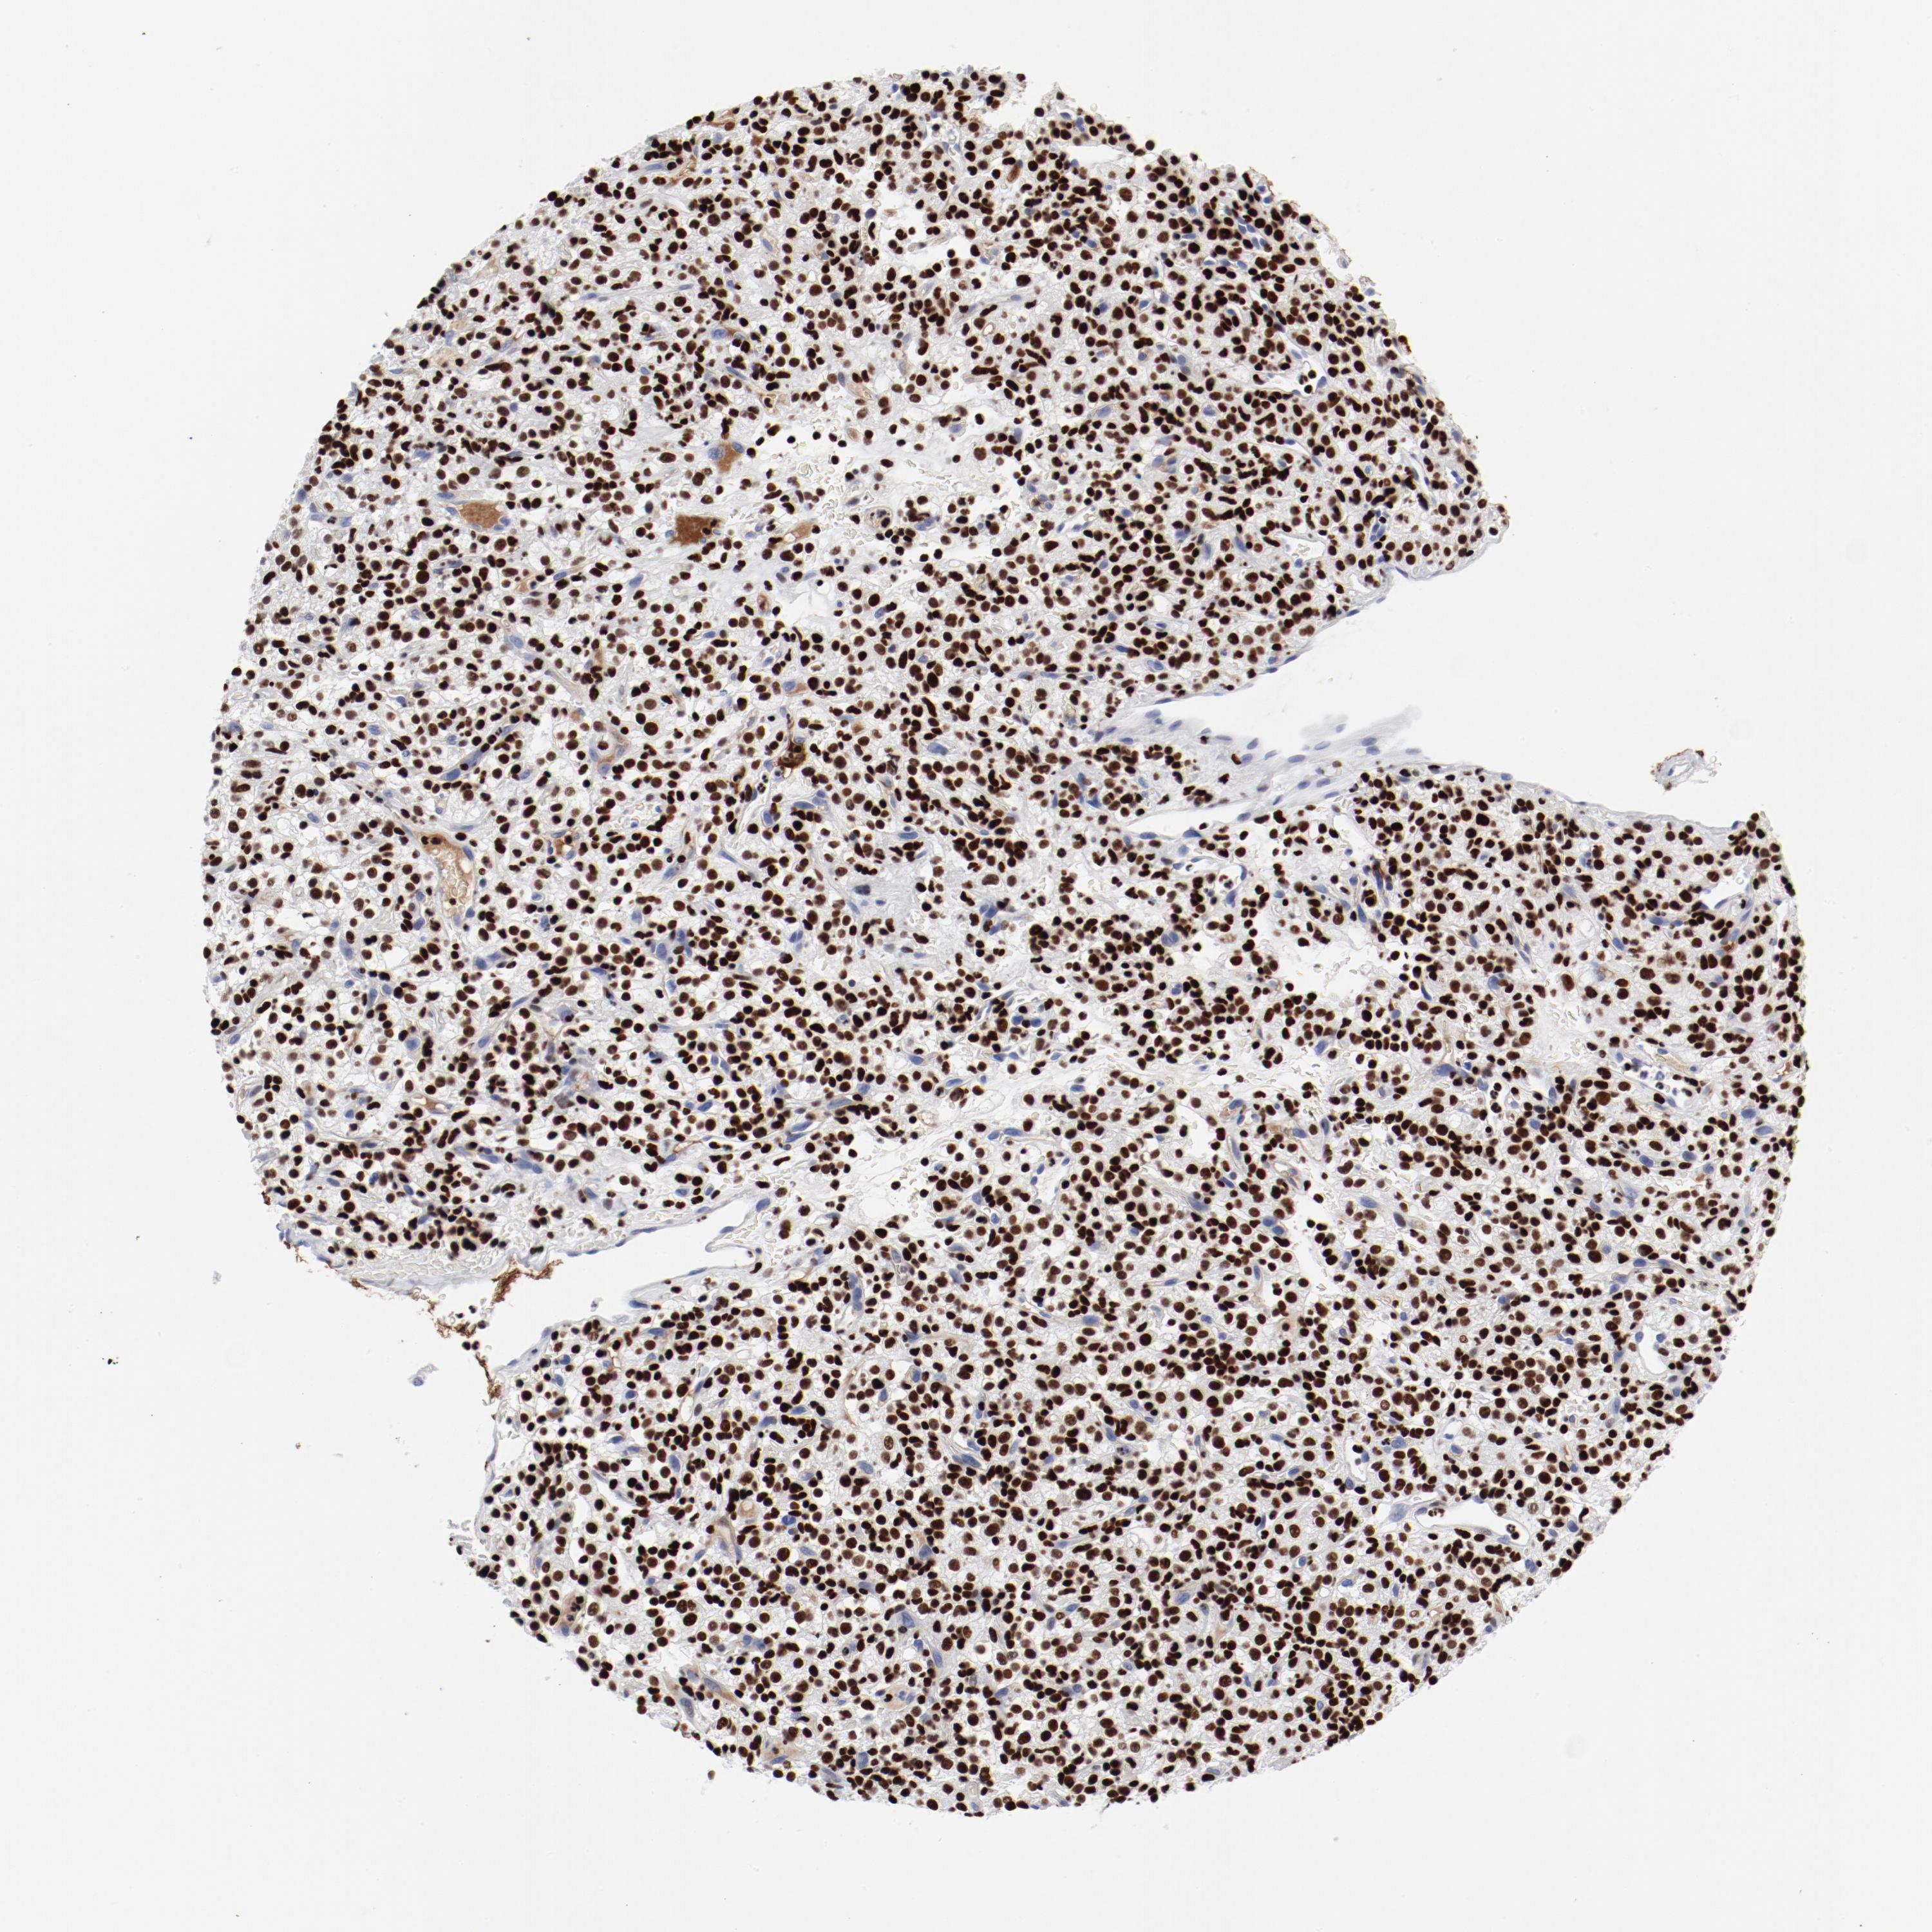

KIDNEY RENAL CLEAR CELL CARCINOMA (TCGA) - Interactive survival scatter ploti

The Survival Scatter plot shows the clinical status (i.e. dead or alive) for all individuals in the patient cohort, based on the same data that underlies the corresponding Kaplan-Meier plots. Patients that are alive at last time for follow-up are shown in blue and patients who have died during the study are shown in red.

The x-axis shows the expression levels (FPKM) of the investigated gene in the tumor tissue at the time of diagnosis. The y-axis shows the follow-up time after diagnosis (years). Both axes are complimented with kernel density curves demonstrating the data density over the axes. The top density plot shows the expression levels (FPKM) distribution among dead (red) and alive patients (blue). The right density plot shows the data density of the survived years of dead patients with high and low expression levels respectively, stratified using the cutoff indicated by the vertical dashed line through the Survival Scatter plot. This cutoff is automatically defined based on the FPKM cutoff that minimizes the p-score. The cutoff can be changed by dragging the vertical line or by entering a cutoff value in the square labeled "Current cut-off".

Under the Survival Scatter plot the p-score landscape (black curve; left axis) is shown together with dead median separation (red curve; right axis). Dead median separation is the difference in median mRNA expression between patients who have died with high and low expression, respectively. It is calculated as follows: median FPKM expression of dead patients with high expression - median FPKM expression of dead patients with low expression. This is intended to aid the user in visually exploring custom cutoffs and the associated p-scores and dead median separation.

Individual patient data is displayed and can be filtered by clicking on one or more of the category buttons on the top of the page. Categories describing expression level and patient information include: high, low, alive, dead, female, male and tumor stages. The scale of the x-axis can be toggled between linear and log-scale by clicking on the "x log" button. Mouse-over function shows TCGA ID, patient information and mRNA expression (FPKM) for each patient.

& Survival analysisi

Kaplan-Meier plots summarize results from analysis of correlation between mRNA expression level and patient survival. Patients were divided based on level of expression into one of the two groups "low" (under cut off) or "high" (over cut off). X-axis shows time for survival (years) and y-axis shows the probability of survival, where 1.0 corresponds to 100 percent.

SMARCC2 is not prognostic in Kidney Renal Clear Cell Carcinoma (TCGA)

Best expression cut offi

Based on the FPKM value of each gene, patients were classified into two groups and association between prognosis (survival) and gene expression (FPKM) was examined. The best expression cut-off refers the FPKM value that yields maximal difference with regard to survival between the two groups at the lowest log-rank P-value. Best expression cut-off was selected based on survival analysis .

When clicking on this number, the vertical dashed line indicating cut-off, the interactive survival plot, and the Kaplan-Meier curve will be adjusted to show results based on the best expression cut-off.

: 32.12

P scorei

Log-rank P value for Kaplan-Meier plot showing results from analysis of correlation between mRNA expression level and patient survival.

N/A

5-year survival highi

5-year survival for patients with higher expression than the expression cutoff.

For melanoma and glioma, 3-year survival is shown.

5-year survival lowi

5-year survival for patients with lower expression than the expression cutoff.

TCGA RNA samplesi

RNA-seq data is reported as average FPKM (number Fragments Per Kilobase of exon per Million reads), generated by the The Cancer Genome Atlas (TCGA) .

Normal distribution across the dataset is visualized with box plots, shown as median and 25th and 75th percentiles. Points are displayed as outliers if they are above or below 1.5 times the interquartile range. FPKM values of the individual samples are presented next to the box plot.

Average pTPM 35.4

Number of samples 521